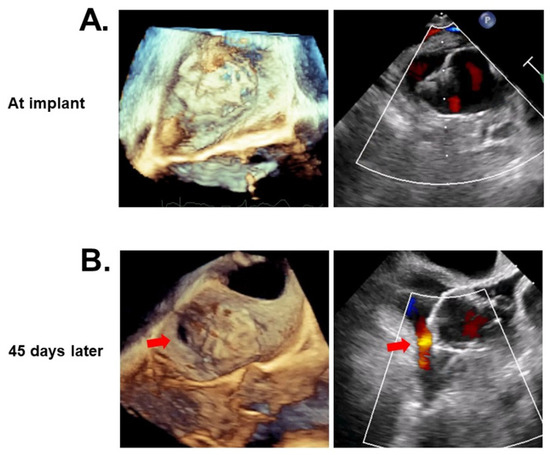

3.4. Clinical Events